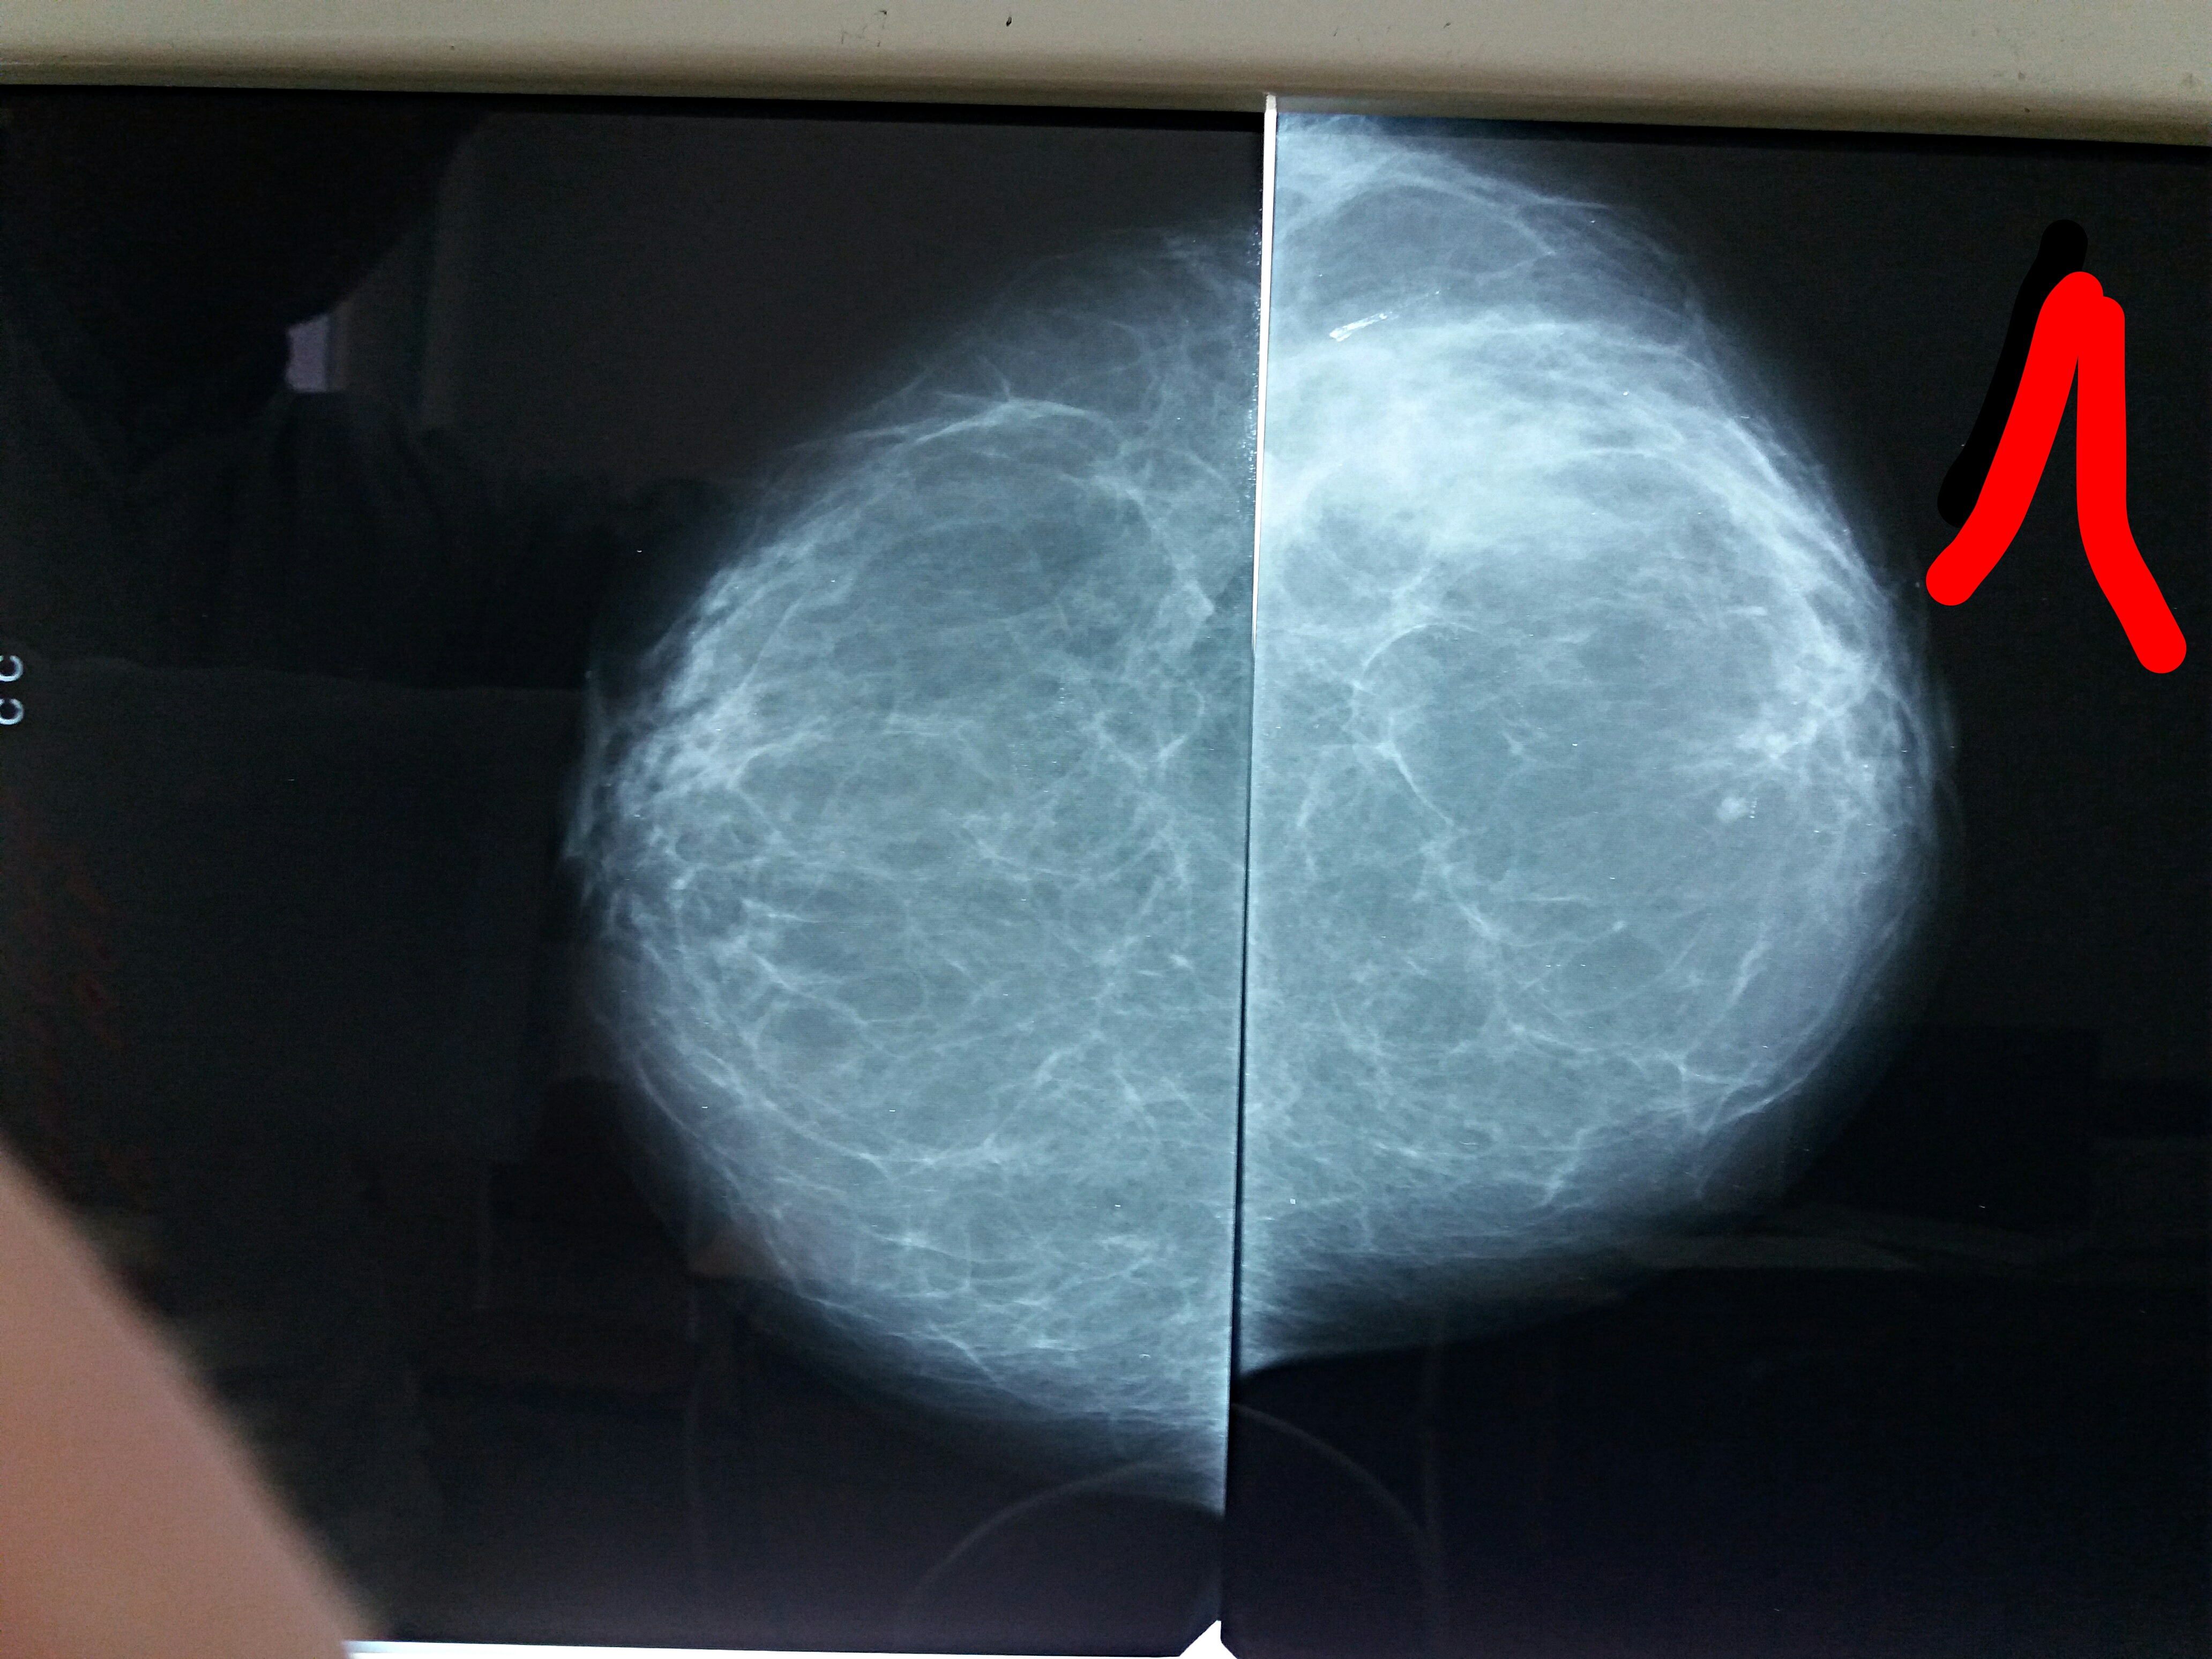

Фиброаденома молочной железы - доброкачественное образование, которое часто встречается у женщин. Оно может быть обнаружено при помощи различных методов диагностики, включая маммографию. Ниже представлены фотографии, помогающие понять, как выглядит данное заболевание.

Маммография и ее роль в диагностике фиброаденомы молочной железы

Маммография - это рентгенологическое исследование молочных желез. Оно позволяет выявить различные изменения в тканях, включая фиброаденому. На маммограммах можно увидеть структурные особенности опухоли и отследить ее динамику во времени.